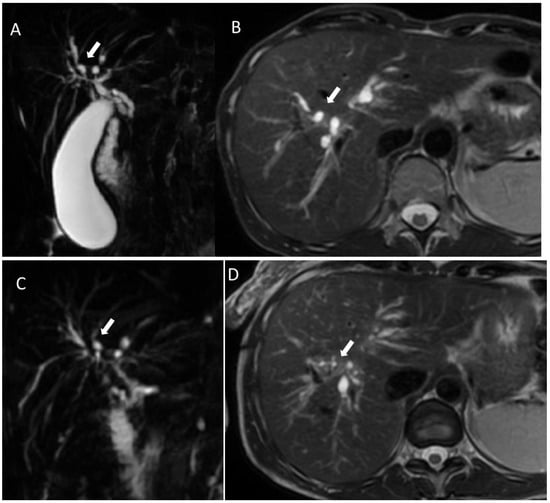

3. Primary Sclerosing Cholangitis

4. Fibropolycystic Liver Disease

6.2. Intraductal Papillary Neoplasia of the Bile Duct

6.5. Diagnostic Management